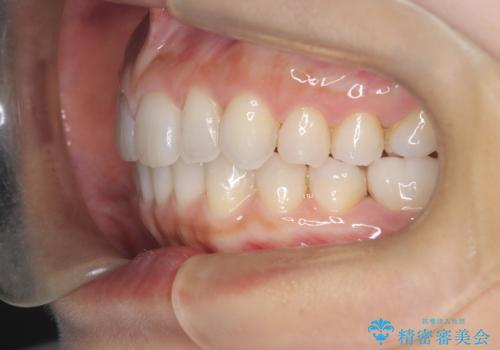

【インビザライン】前歯のねじれを治したい

- 前歯のガタガタを主訴に来院されました。

叢生の量は軽度でしたが臼歯の遠心移動を行い、インビザラインにて治療をしました。

叢生の改善に必要なスペースは遠心移動やIPRで作ることが可能です。今回は遠心移動をメインにスペースを作って叢生の改善を行いました。